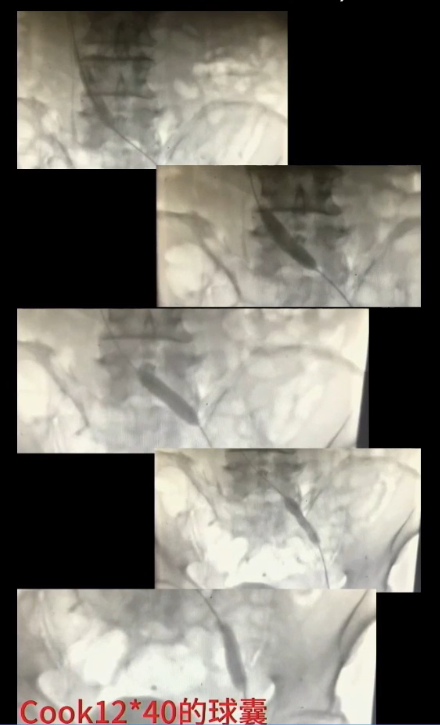

手术过程(四):退出抽吸导管后,复查造影,股浅静脉内血栓消失,但血流速度仍缓慢,提示近心端仍有梗阻。使用高压球囊扩张髂静脉,可见髂总静脉明显狭窄。分段扩张完成后,引入12 mm×40 mm球囊继续扩张。

手术过程(五):复查造影见髂总静脉处仍狭窄,与家属沟通后,同意置入支架。引入髂静脉支架,定位准确后,谨慎释放,12 mm×40 mm球囊扩张髂静脉支架。